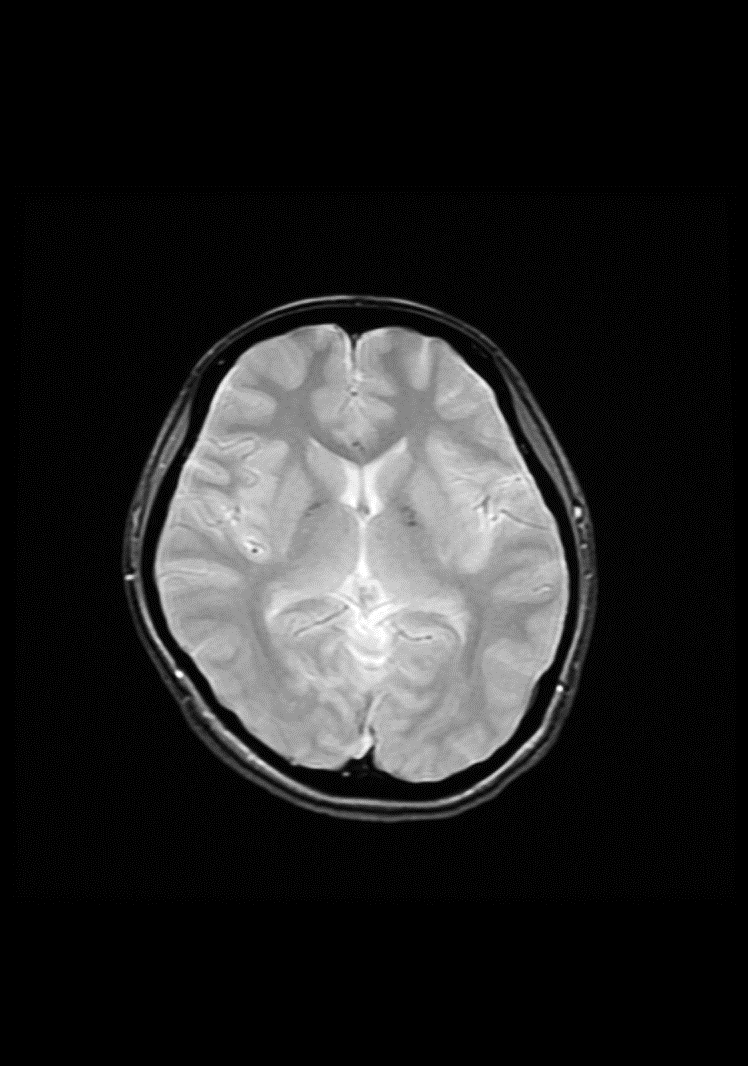

専用 脳MRI 3 高性能MRI(1.5テスラ)|施設・設備|おおたけ脳神経・漢方内科の詳細情報

高性能MRI(1.5テスラ)|施設・設備|おおたけ脳神経・漢方内科。今回導入された3T-MRIについて|名古屋セントラル病院。1.5T MAGNETOM ESSENZA 頭頸部領域における質の高い診断と検査。

「脳MRI3」

MRI | 三島総合病院 | 地域医療機能推進機構